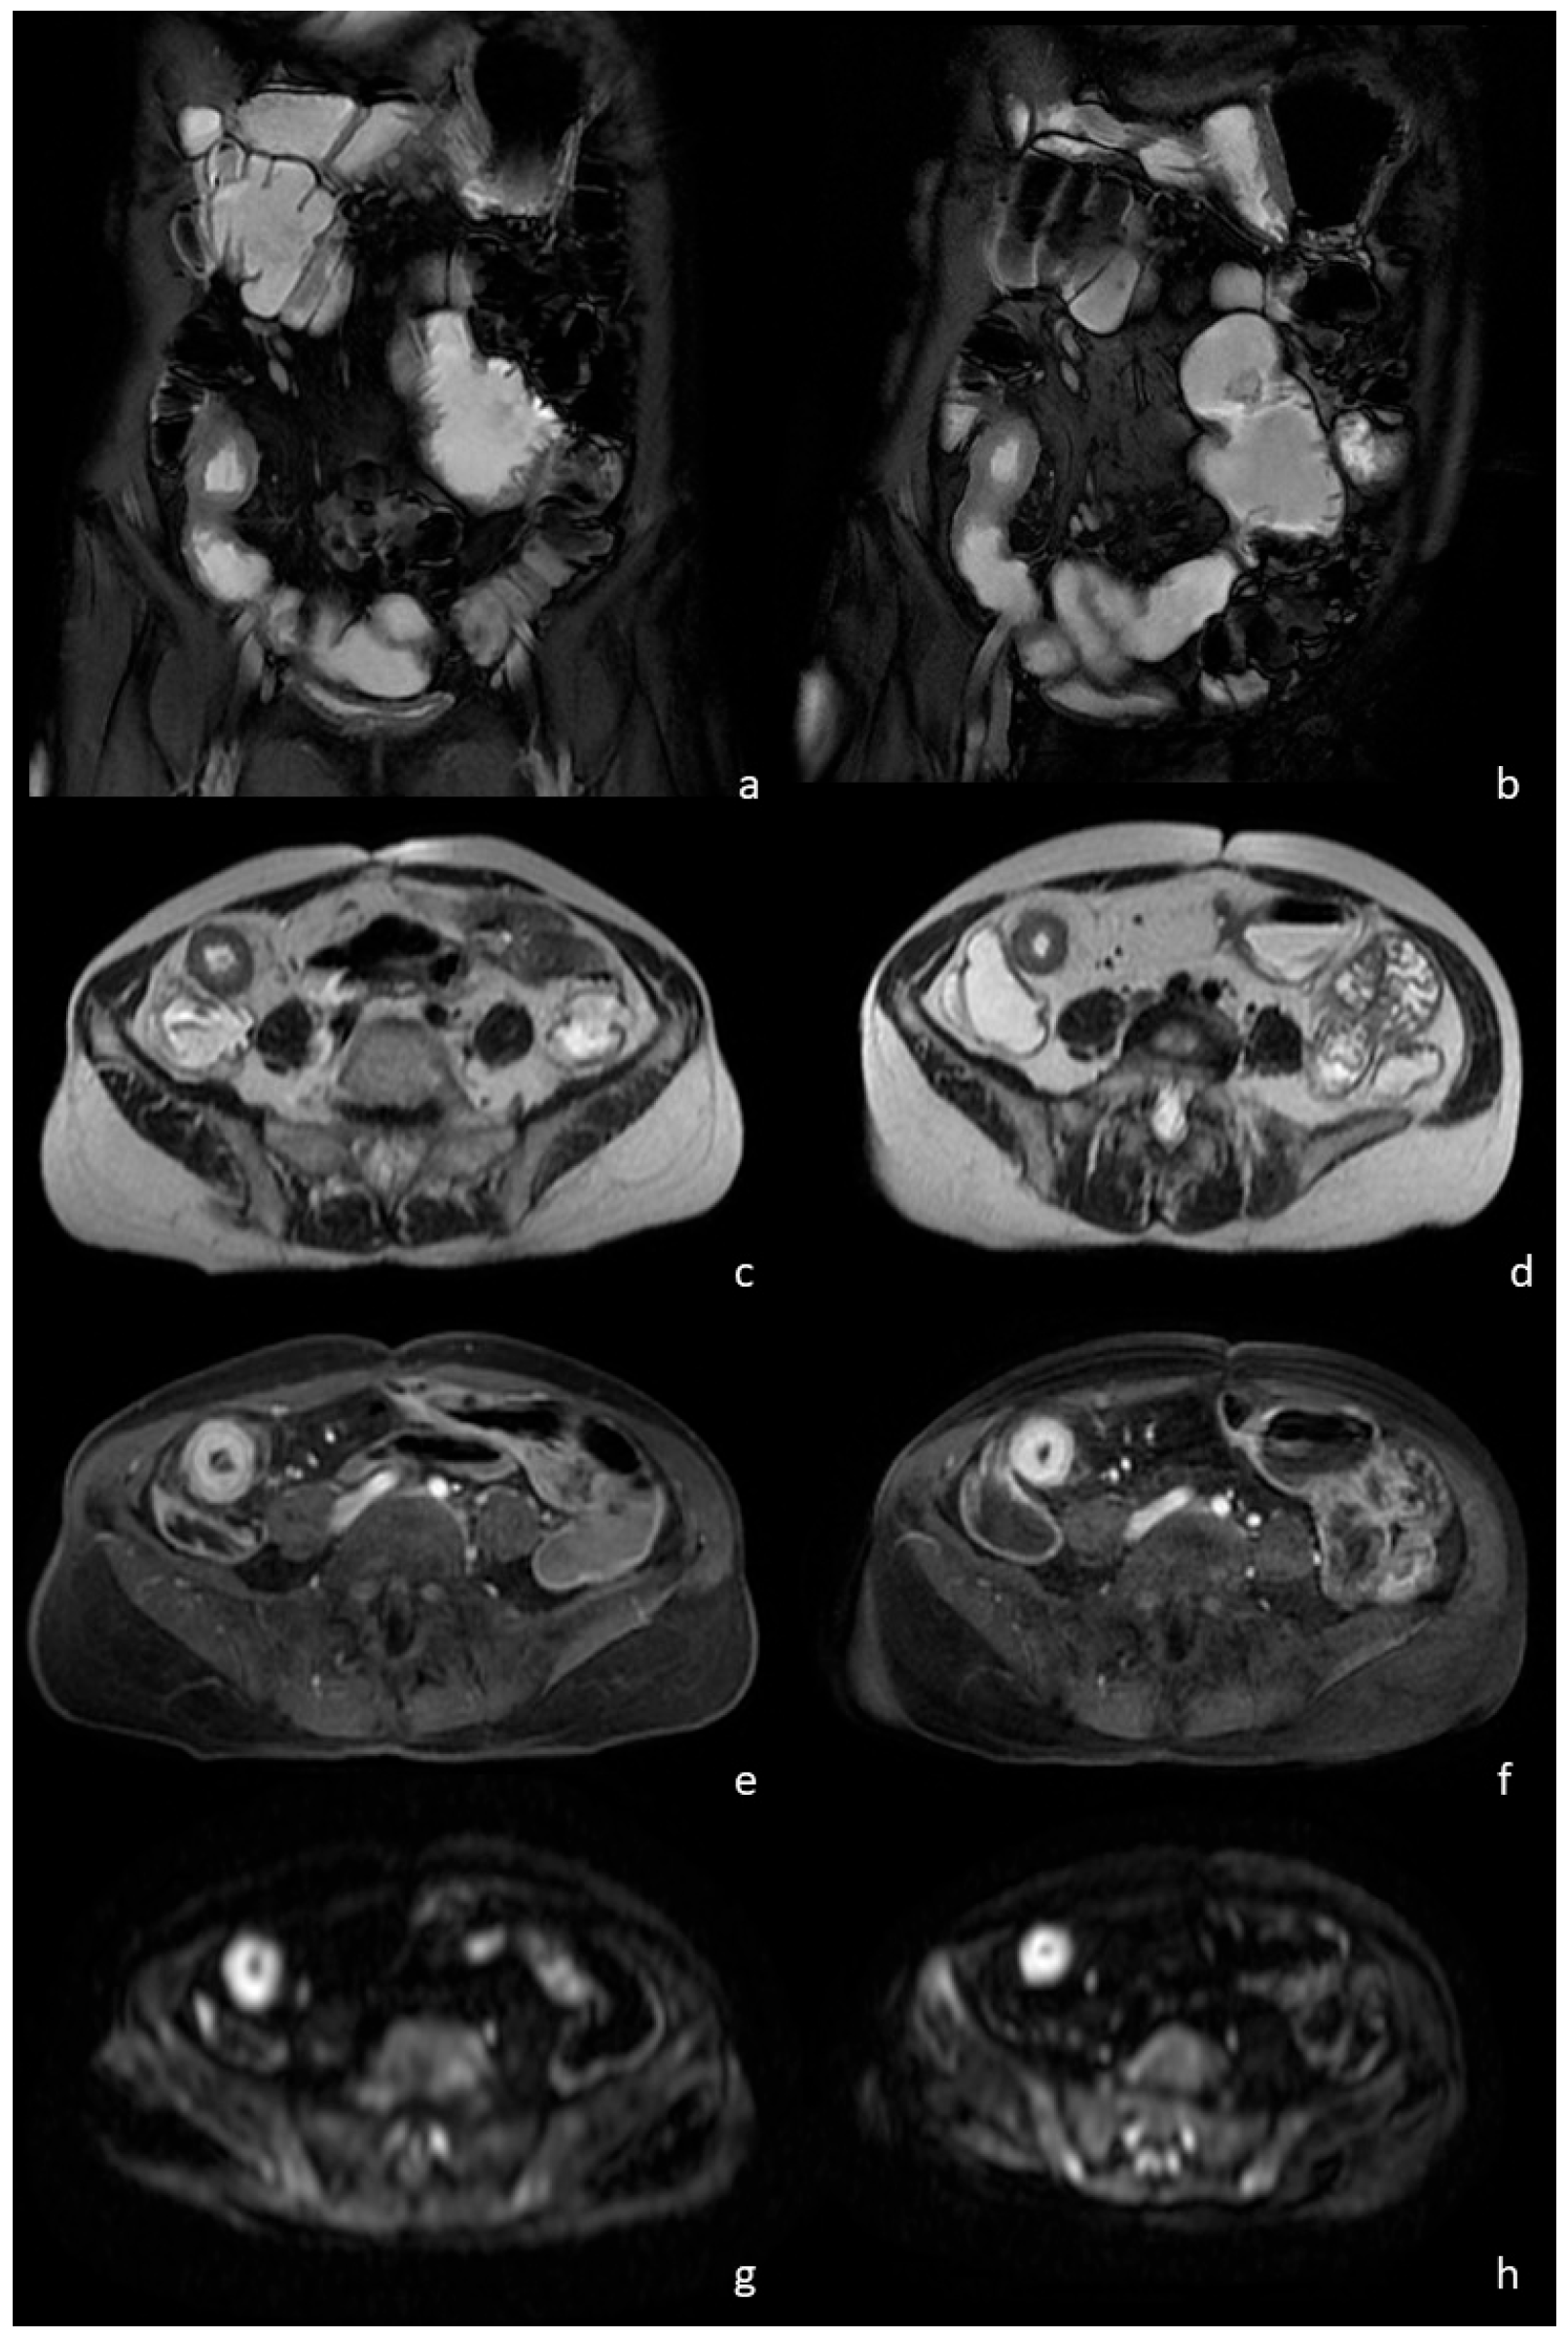

Table 3 shows data regarding the comparison between the evaluations carried out by the two expert radiologists concerning the degree of intestinal distention in the entire study population after the consumption of Isocolan® and Bever1one. In general, the majority of the examinations, including those carried out after Isocolan® (97.1%) and those after Bever1one (94.3%), achieved excellent or good intestinal distension, without significant differences between the readers (Figure 1).

Figure 1. A 32-year-old female patient with a known history of Crohn’s disease. The coronal T2-w with fat saturation sequence shows a narrowing of the last ileal loop caused by a severe wall thickening in both the MRE performed with the PEG water solution (a) and the study performed with the natural beverage (b). No differences regarding intestinal distension and image quality were observed also on the axial T2-w images (c,d). The same segment showed an intense mural hyperenhancement after intravenous contrast injection (arrows), regardless of the oral contrast used, the PEG water solution (e) or the natural beverage (f). Hyperintensity on the axial DW images was observed in both groups (g,h), without significant differences due to the different oral contrast administrated.